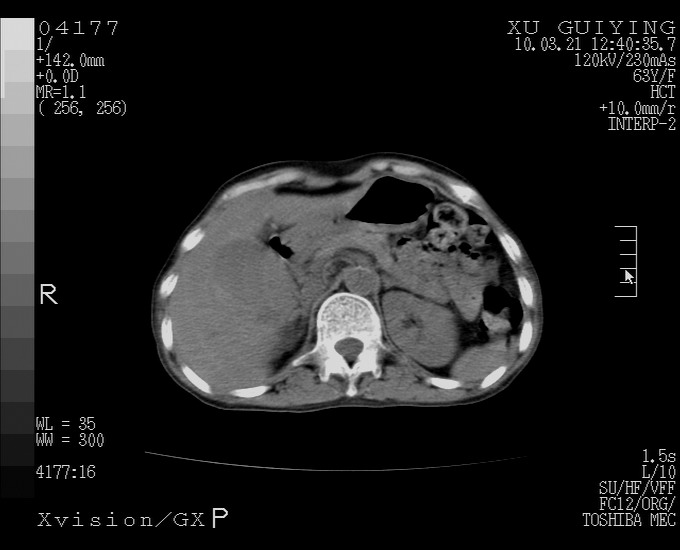

怎么没有增强呢?胆囊那么大,密度有些高啊。

胆囊体积增大,胃窦壁增厚

胆囊体积增大,密度不均匀,结石不除外;胃壁增厚,考虑胃癌,建议增强。

胆囊体积增大,密度增高,较均匀,外缘也较光滑,应考虑胆囊炎。因为胃未充盈,不好说壁增厚。肝左叶及脾门处见低密度灶,有可能是血管瘤,不排除囊肿。建议超声检查或强化。